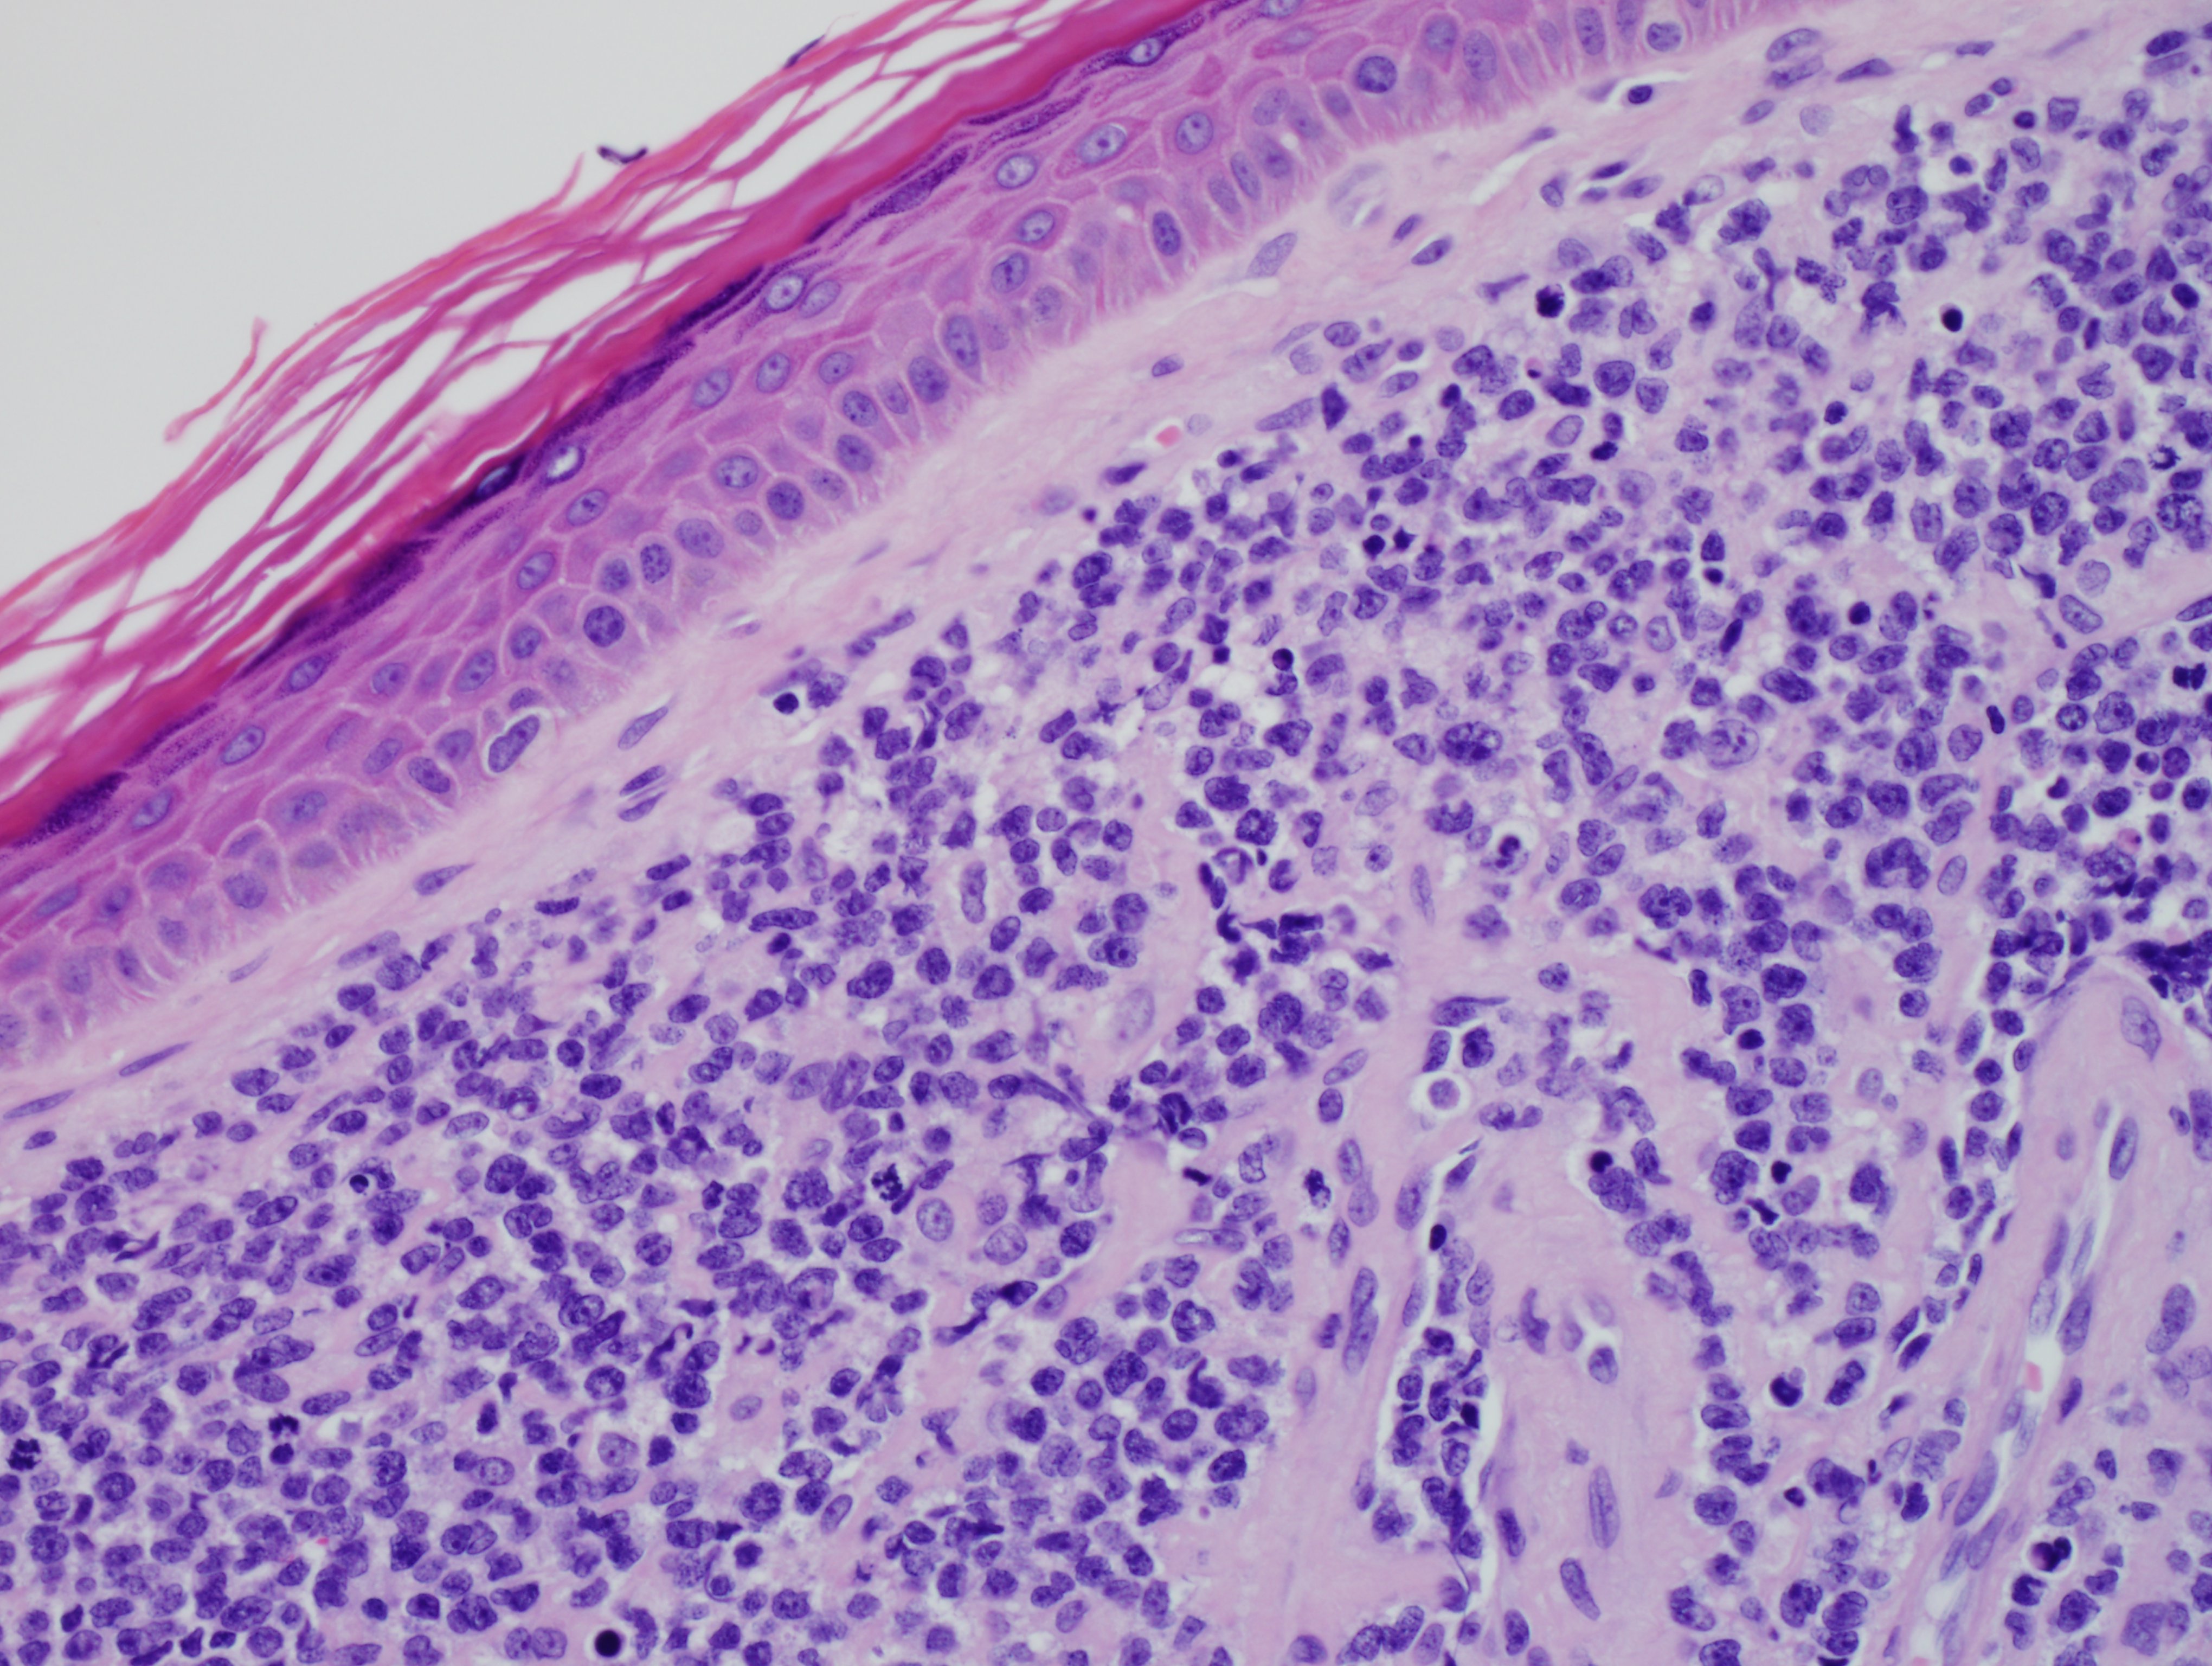

Morphologically, BPDCN is characterized by a diffuse infiltrate of blastoid, monomorphic and medium-sized cells with scant cytoplasm, irregular nuclei, fine chromatin, and nucleoli. Mitoses are typically present and necrosis is usually absent. With cutaneous manifestations, epidermotropism is not observed. Tumor cells typically express CD4, CD7+/-, CD56, CD123, CD303, TCL1, and CD43. Very rarely, CD56 can be negative. CD33, CD79a, BCL2, and BCL6 can also be expressed. T-cell and B-cell receptor genes are usually germline. Several recurrent chromosomal abnormalities have been noted, such as 5q21/5q34, 12p13, and 13q13-21.